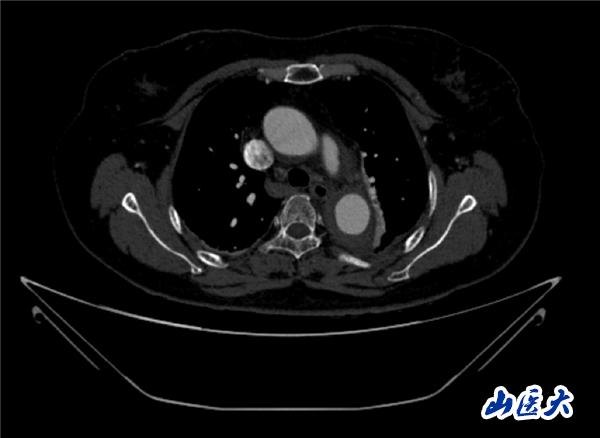

首例患者是一位55岁的女性,她患有高血压约2年时间,平时也会规律服用多种降压药,但血压控制始终不尽人意。2023年4月下午,她出现不明原因的头痛,在家拔罐缓解少许便未到医院就医,次日凌晨突感胸闷、胸背疼痛伴有呼吸困难等症状、家人急忙拨打了120,把患者送入医院急诊科进行救治,医生在急诊科行胸腹主动脉CTA时,显示主动脉弓部-降主动脉及腹主动脉壁间血肿,遂收治入医院血管外科,患者入院10天后复查血肿仍未有改善,依然伴有胸背部疼痛等不适,如不进一步处理,可能发展为夹层危及生命,患者及家属经过与医生团队了解沟通,决定进行创伤小、恢复快的介入手术治疗。张玮教授、符伟国教授、董红霖教授及其血管外科团队(闫盛、常文凯、田琴琴)共同商讨手术方案,最终确定使用Zipper™一体式主动脉弓覆膜支架系统,行胸主动脉覆膜支架腔内隔绝术+无名动脉、左颈总动脉、左锁骨下动脉分支重建术为患者进行治疗。董红霖教授及其血管外科团队根据患者术前头颅CT平扫提示双侧侧脑室旁缺血灶,血压控制不稳定,属夹层壁间血肿非典型夹层等风险点,制定了完整的手术方案,术中经股动脉置入Zipper支架主体,经预留导丝超选无名动脉,并确保主体支架对位准确,顺利置入左颈总动脉、左锁骨下动脉支架,重建弓上三分支。手术过程非常顺利。术后观察主动脉及分支覆膜支架定位准确;无内漏;分支支架通畅,动脉供血正常。

术后效果